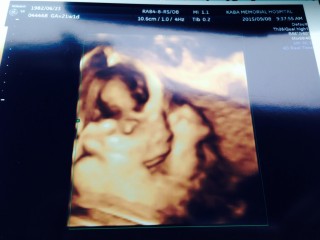

4Dだけ撮ってもらいに別の産婦人科に行ってきました。お顔を見せてくれるかドキドキでしたが、もうバッチリ見せてくれました☆なんて親孝行!偉いって先生に褒められました(*^o^*)500グラムくらいで順調とのことで良かったです!